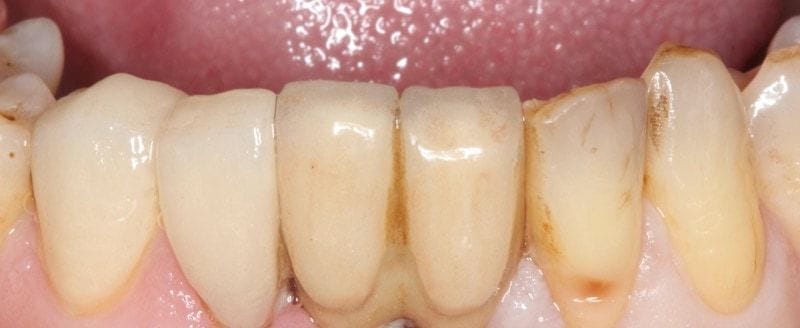

他對右下兩顆用全瓷修復的成果感到非常美觀且滿意,陸續開始計畫接受左下的側門牙和犬齒的全瓷貼片療程,以及評估上顎前牙美觀區全瓷貼片的條件。

圖示:完成全瓷貼片的左下側門牙和犬齒